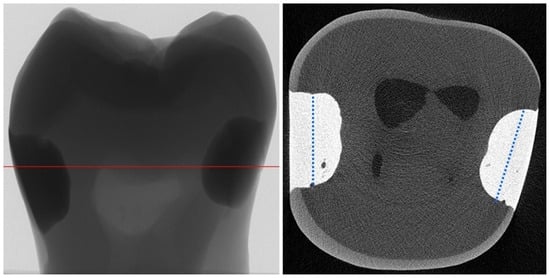

4.1. Thermomechanical Loading (TML) and Water Degradation Analysis

4.2. Micro-Computed Tomography (µCT) Analysis